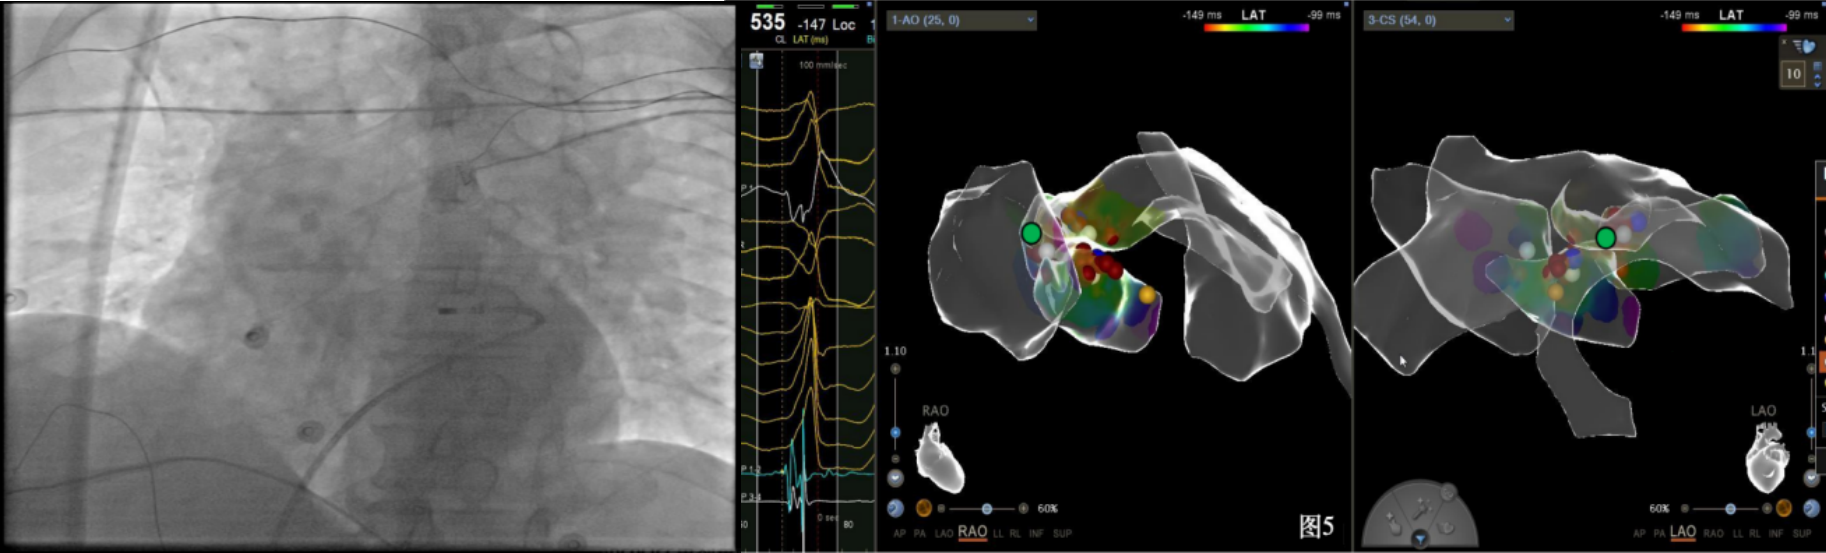

即穿刺股静脉,将消融大头送至冠状窦内,在GCV远端对应位置标测到最早点(图5绿色点)领先体表27ms,消融后早搏未能消失,周明礼评估起源点偏心外膜,能量依旧不能穿透损伤到起源点,内膜消融基本无效后,果断选择难度系数最为复杂的干性心包穿刺心外膜消融。在导丝的指引下,将消融大头送至心包层(图6),于外膜标测到靶点(图7黄色点)电位领先体表31ms,单极电位无r波且有顿挫,ssummit外膜离冠状动脉较近,比较危险,保证安全,进行了冠脉造影(图7),显示距离LAD和LCx有一定距离,相对安全,随即放电,2s室早消失,10s患者出现心率变慢,该区域走形迷走神经节,消融导致心率减慢,随后保证心率正常的情况下,消融够60s,随后观察半小时,早搏没有恢复,手术成功(图8)。经过不懈的努力,患者恢复了窦率,心脏功能也逐渐恢复正常,手术取得了圆满成功。